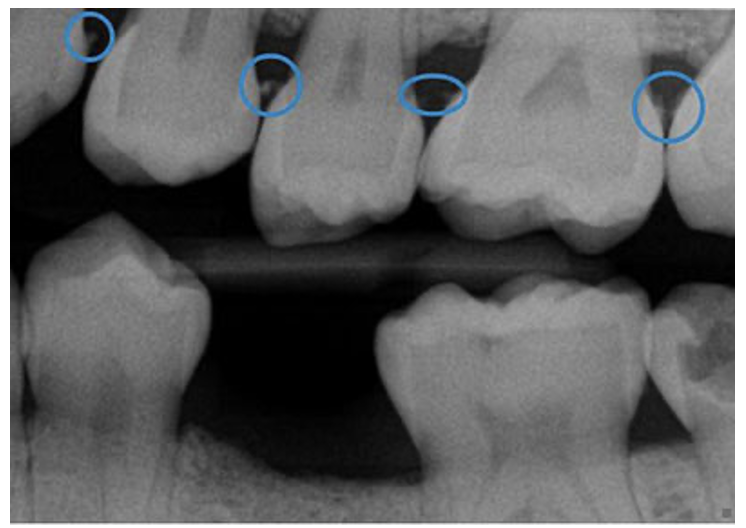

Gum disease, or periodontitis, is diagnosed by evaluating x-rays for the loss of the bone that holds the teeth in place, and by doing a clinical exam to evaluate if the gums are inflamed and/or bleeding. Both parts of the exam are necessary to come to a diagnosis; neither one on it’s own provides enough information to form a diagnosis or a treatment plan.

The straight line in the picture above shows where the bone level should be in a healthy patient. The wavy line shows where the bone actually is. The black spaces in between show the areas where bone has been lost.

Sometimes people have xrays that look like the picture above but they do not need a deep cleaning. This happens when they have had gum disease in the past, and have already suffered some bone loss, but have received treatment and are now stable. The bone does not grow back, but as long as the gums are not inflamed, we know that they do not have active gum disease.

Other times, the bone loss is minor but there is heavy tartar buildup underneath the gums which causes them to be inflamed and bleed. This would be the early stages of gum disease and would be treated with a deep cleaning.